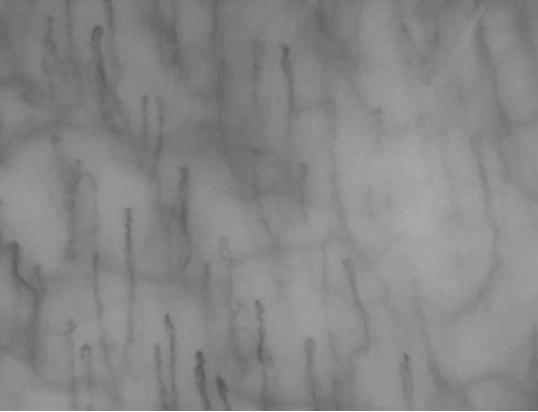

Una geografia invisibile: i piccoli canali del sangue

Se ci spostiamo dai muscoli alla superficie che riveste l’interno della nostra bocca, entriamo in un mondo microscopico fatto di “autostrade del sangue”: i capillari; questi minuscoli vasi sono i primi a risentire dei cambiamenti nell’equilibrio dell’organismo. Oltre agli aspetti biomeccanici, infatti, la fibromialgia sembra lasciare una “traccia” microscopica nei tessuti molli della bocca. Lo studio “Evaluation of Oral Mucosa Capillaries in Fibromyalgia Patients” (2) ha utilizzato la videocapillaroscopia della mucosa orale, una tecnica d’indagine in vivo non invasiva che permette di osservare in tempo reale la morfologia dei piccoli vasi sanguigni. Esplorando la mucosa orale si scopre una impronta morfologica peculiare, tale per cui la rete di questi piccoli vasi appare alterata: la lunghezza capillare è risultata, nel campione analizzato, significativamente ridotta e l’orientamento capillare variegato, come se la “mappa” della microcircolazione avesse subito un ridimensionamento.